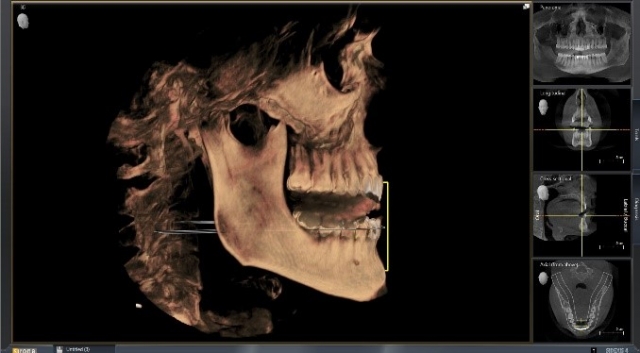

If you are planning on using software like SicatAir to compare airway volume at that position compared to maximum intercuspation, then it might be a good idea to leave the silicone, and you could even take out the lower part of the bite fork, allowing the patient to bite solidly into the material (Figs. 9–12).

That entire digital file can then be uploaded and sent to fabricate an appliance, capturing the position of the mandible, while confirming the anticipated volume (yes, I know the patient is awake and sitting up. If you find a way to take a scan with the patient supine and asleep, it would be even better, right?) (Fig. 13)